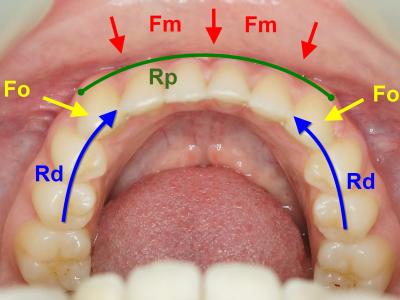

Plusieurs forces agissent sur cette région :

- Les forces musculaires (Fm) du complexe labio-mentonnier. Elles sont essentiellement centripètes et s’étendent comme les insertions musculaires de la canine à la canine.

- Les forces occlusales (Fo) avec les incisives et canines maxillaires. Egalement centripètes, elles sont en plus d’être verticales, sagittales en incision, et plus transversales en mastication

Elles rencontrent deux résistances :

- La résistance mécanique du complexe dentaire (Rd), ou sa capacité à résister au déplacement

- La résistance mécanique du parodonte (Rp), dépendante du biotype parodontal

Ce système mécanique forme une arche dans laquelle les dents sont l’armature, le parodonte le liant et les forces musculaires et occlusales la charge mécanique à soutenir. Ce système est donc comparable à celui d’une arche en architecture (figure 2a et b).

Situations mécaniques possibles :

- Rd ≥ (Fm + Fo) et Rp ≥ (Fm + Fo) : situation d’équilibre

- Rp ≥ (Fm + Fo) > Rd : déséquilibre mécanique avec conséquences dentaires

- Rd ≥ (Fm + Fo) > Rp : déséquilibre mécanique avec conséquences parodontales

- (Fm + Fo) > Rd et (Fm + Fo) > Rp : déséquilibre mécanique avec conséquences dentaires et parodontales

Figure 2 : similitude mécanique entre une arche (a) et la région incisivo-canine mandibulaire (b)